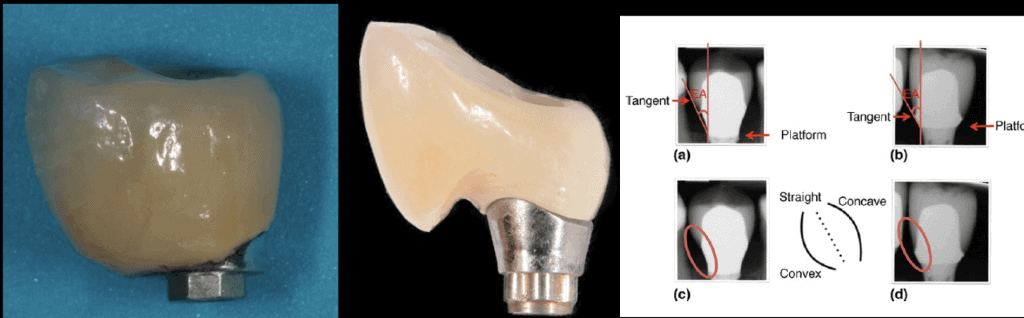

Every technical construction has gaps between its components. Implant, abutment, screws, prosthesis, they all come with certain gaps, sometimes acting protectively and sometimes to the detriment of the complex.

They can be “microgaps” of 1-2 μm or “megagaps” of 100 μm, they can be deep near the bone, or high up in the sulcus, sugingival or supragingival. Knowing which gaps to accept and which to avoid is essential, as this is a risk that can be minimised through the correct design of the prosthesis and selection of implant and prosthetic components!

Nr. 5: Stay in shape !

The “emergence profile” is a key for long term success and its optimal shape and size is crucial. Depth or height, Concavity or Convexity, angles of emergence, these are all design features we need to plan in advance before the implant is even placed. Otherwise, compromise and trouble is inevitable.